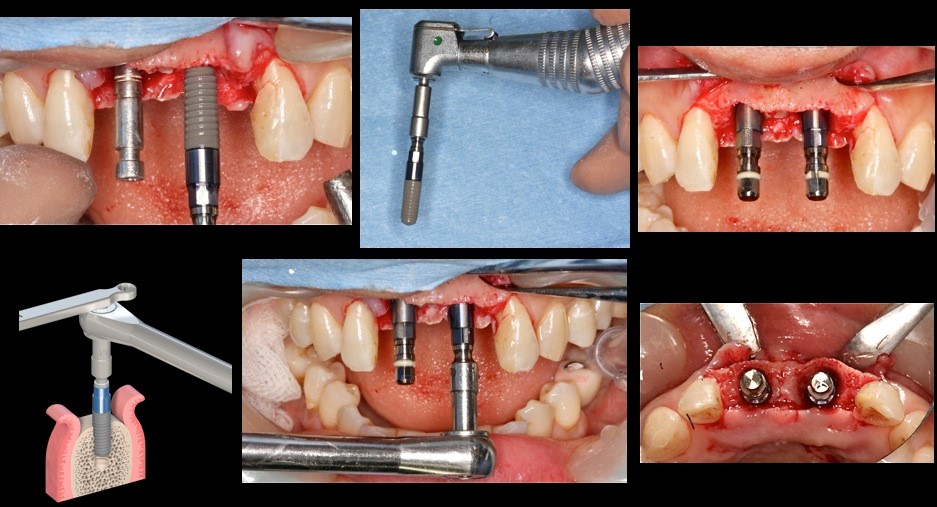

ガイドサージェリーのスターティングに また形成にもガイドの動揺を最小限にすることができる。ひいては所定の位置に近い埋入が可能になる

傾斜埋入の際の形成にもドリルのずれが無く、ガイドを揺さぶることも起こりにくい

フライスドリルは骨質の不均一な部位に応用する

温故知新 従来のマウントでガイドを固定している